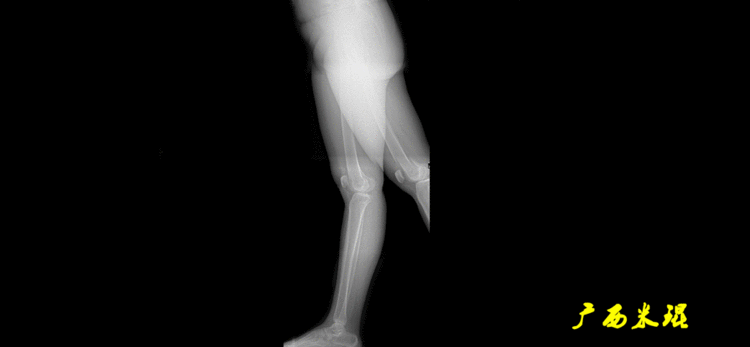

下肢力线及相关角度测量的前提是必须拍摄标准的站立位也就是负重位的下肢全长片。目前这样的照片都是放射科的技师在电脑上拼接出来的,大部分医院的DR都能够做到这一点。

患者直立于摄影架上,后背贴近摄影架,双手自然下垂,膝关节尽量伸直,足部与双肩同宽,要求投照时双髌骨朝正前方,通常患者双足尖应平行向前即可。

提醒一下大家,拍摄过程中应避免下肢的外旋和内旋。如果有一侧肢体短缩时,投照应当用脚垫垫高短缩肢体,使骨盆保持水平,这样下肢短缩测量才精确。如果有肢体旋转畸形时,还是以髌骨朝前为标准,虽然此时双足可能不能保持平行。

无论如何,拍摄出来的下肢全长片必须包含髋关节中心、膝关节中心及踝关节中心,否则对临床是无用的。有了一张下肢的全长照片,我们需要确定下肢关节的中心点,通过中心点画出下肢的各种轴线,然后利用轴线与关节线的相交得出各种所需要的角度。